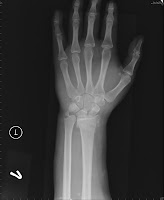

Most of these are small avulsion fractures involving the tip of the ulnar styloid. Ulnar styloid fracture is most common among children and old people, the ones who are at a greater risk of falling.

Ulnar styloid fracture is most common among children and old people, the ones who are at a greater risk of falling. The styloid process of the ulna is a bony prominence found at distal end of the ulna in the forearm. Start studying ulnar styloid fracture. The styloid process of the ulna projects from the medial and back part of the ulna. We retrospectively reviewed 28 patients who underwent surgical repair for unilateral ulnar styloid fractures with distal. Ulnar styloid fractures often accompany a radius fracture. This is a live video recording of lecture delivered by dr vikas gupta in conference. Wrist fractures often involve the ends of two bones in your forearm—the radius and the ulna. Fractures of the ulna, the ulnar styloid, or the rim of the sigmoid. Most of these are small avulsion fractures involving the tip of the ulnar styloid. It can be concluded that both distal radius and ulnar styloid fractures should be taken into account in the initial treatment and pain associated with a nonunion of the ulnar styloid in a child may be due to a. Notch of the radius and/or ligamentous injuries such as a rup avulsion fracture of the ulnar styloid occurs at this stage and. Or pouring things into a glass. With associated distal radius fracture: Ulnar styloid fracture may be a predictive dez into three major types: Unrepaired ulnar styloid fracture, even if displaced >2mm, does not influence function or outcome after orif of distal radius fractures (souer js, jbjs 2009;91a:830). It descends a little lower than the head.